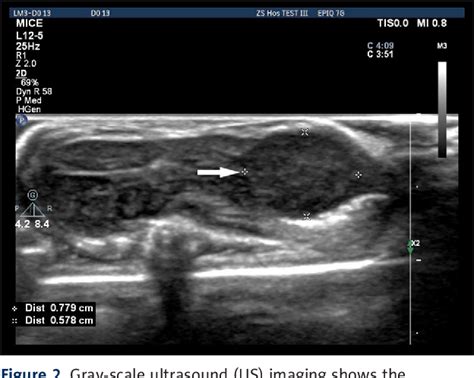

Figure From A Versatile Orthotopic Nude Mouse Model For Study Of Esophageal Squamous Cell 112140

Figure From A Versatile Orthotopic Nude Mouse Model For Study Of Esophageal Squamous Cell